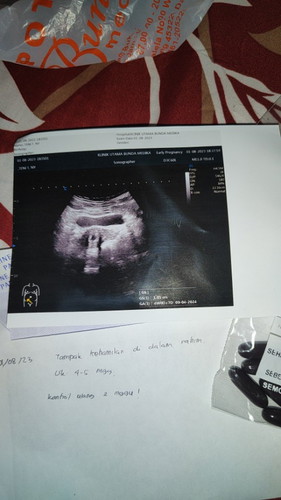

bun kalo hamil 4week hasil usg seperti ini apakah normal bun?🙏 sy hamil anak pertama jdi agak parno

Baca lagiselama di dalam rahim insyaaAllaah normal bun. Di usia 4minggu udah keliatan itu maasyaaAllaah lho bun, karna rata² hasil USG menunjukan penebalan rahim kalau usianya masih 4minggu. Makanya bunda disuruh kontrol kembali 2minggu lagi untuk melihat perkembangannya.. mudah²an hasil yang terbaik ya bunda 🤗 oiya bunda hpht nya kapan emang bun?

Baca laginormal bunda , sampai usia sebelum 8 minggu, rata2 penampakan memang hanya kantong kehamilan saja., poin bagusnya adalah kehamilannya di dlm kandungan, jd kehamilan bs dilanjutkan